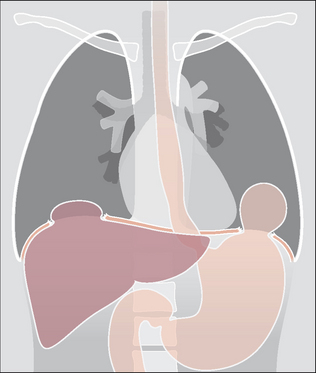

QUESTION 8—IS THE DIAPHRAGM NORMAL?14-17

Rupture of a dome of the diaphragm occurs in approximately 5% of cases of severe thoracic trauma14,16. A rupture is more common with blunt trauma than with a penetrating injury. The mechanism of injury is usually a sudden rise of intra-abdominal pressure from violent compression to the abdomen or lower thorax1.

image A rupture may affect either dome. The left dome is more commonly involved14—in the ratio of 4:1. A few cases are bilateral.

image In 50% or more of cases herniation of abdominal viscera through the rupture is delayed14. Delay may be two or more years after the injury and results from a small tear subsequently increasing in size.

image The following CXR features suggest a tear of the diaphragm2,3,14-17:

image Gas-containing viscus in the thorax (Figs 32.17 and 32.18).

image Abnormal contour of a dome (Fig. 32.18).

image A significant change to the shape of a dome compared with a previous normal CXR.

image Left dome: tip of a nasogastric tube situated unusually high.

image Right dome: small haemothorax with an unexpectedly high dome.

Figure 32.18 Rupture of both the right and left domes of the diaphragm. The diaphragm is injured in approximately 5% of severe thoracic injuries14,16 and 22% of all thoraco-abdominal injuries3. Some 33% of these injuries are diagnosed three years after the trauma…sometimes because the abnormal CXR features were previously overlooked3. The most common site of injury is at the apex of the left dome.